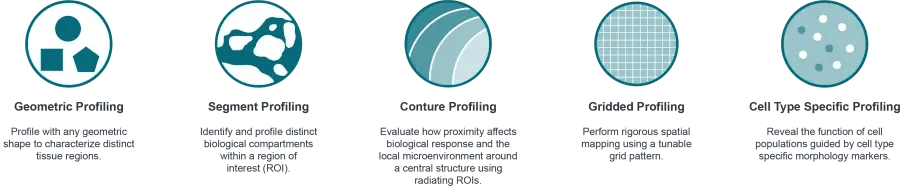

Efficiently address tissue diversity and intricate micro-environments using the GeoMx Digital Spatial Profiler (DSP), the premier spatial multiomic platform designed for both FFPE and fresh frozen tissue analysis. Unique in its field, the GeoMx facilitates non-destructive RNA and protein expression profiling from specific tissue sections and cell groups, all through an automated, scalable workflow compatible with conventional histology staining processes.

Efficiently address tissue diversity and intricate micro-environments using the GeoMx Digital Spatial Profiler (DSP), the premier spatial multiomic platform designed for both FFPE and fresh frozen tissue analysis. Unique in its field, the GeoMx facilitates non-destructive RNA and protein expression profiling from specific tissue sections and cell groups, all through an automated, scalable workflow compatible with conventional histology staining processes.